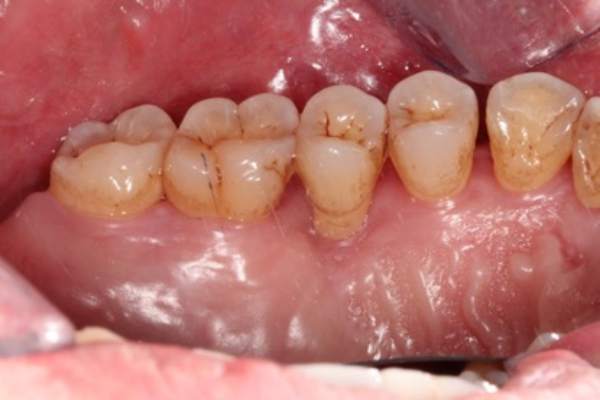

上圖中箭頭所指處因牙齦下結石堆積,因而造成牙齦呈現紅腫狀態。

經由牙周治療去除結石後可見牙齦恢復健康,呈現粉紅色且不再紅腫,但牙齦

消腫後會造成牙齦萎縮,而萎縮程度跟齒槽骨破壞程度相關。